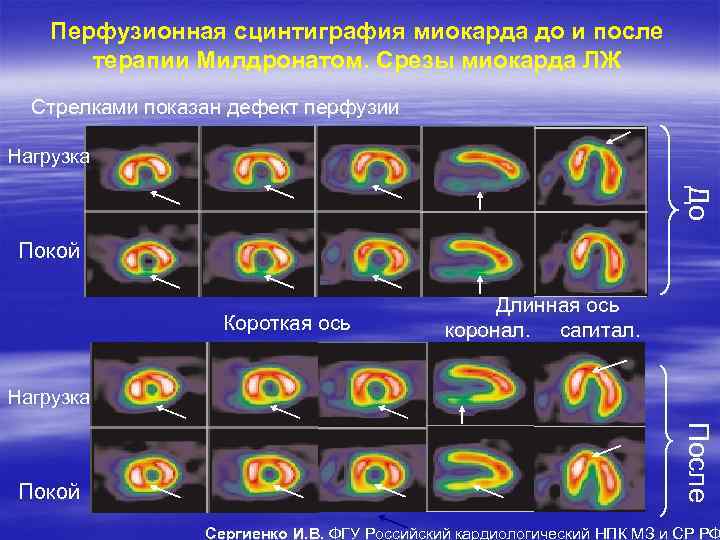

Перфузионная сцинтиграфия миокарда до и после терапии Милдронатом. Срезы миокарда ЛЖ Стрелками показан дефект перфузии Нагрузка До Покой Короткая ось Длинная ось коронал. сагитал. Нагрузка После Покой Сергиенко И. В. ФГУ Российский кардиологический НПК МЗ и СР РФ

Перфузионная сцинтиграфия миокарда до и после терапии Милдронатом. Срезы миокарда ЛЖ Стрелками показан дефект перфузии Нагрузка До Покой Короткая ось Длинная ось коронал. сагитал. Нагрузка После Покой Сергиенко И. В. ФГУ Российский кардиологический НПК МЗ и СР РФ